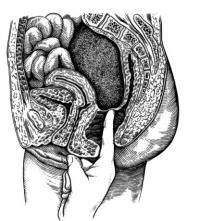

Рис. 87. Пальцевое исследование прямой кишки для выявления абсцесса дугласова пространства

Большую помощь в диагностике гнойника дугласова пространства оказывает пальцевое исследование прямой кишки (рис. 87), сочетающееся с влагалищным исследованием у женщин или с пальпацией нижних отделов живота у мужчин.